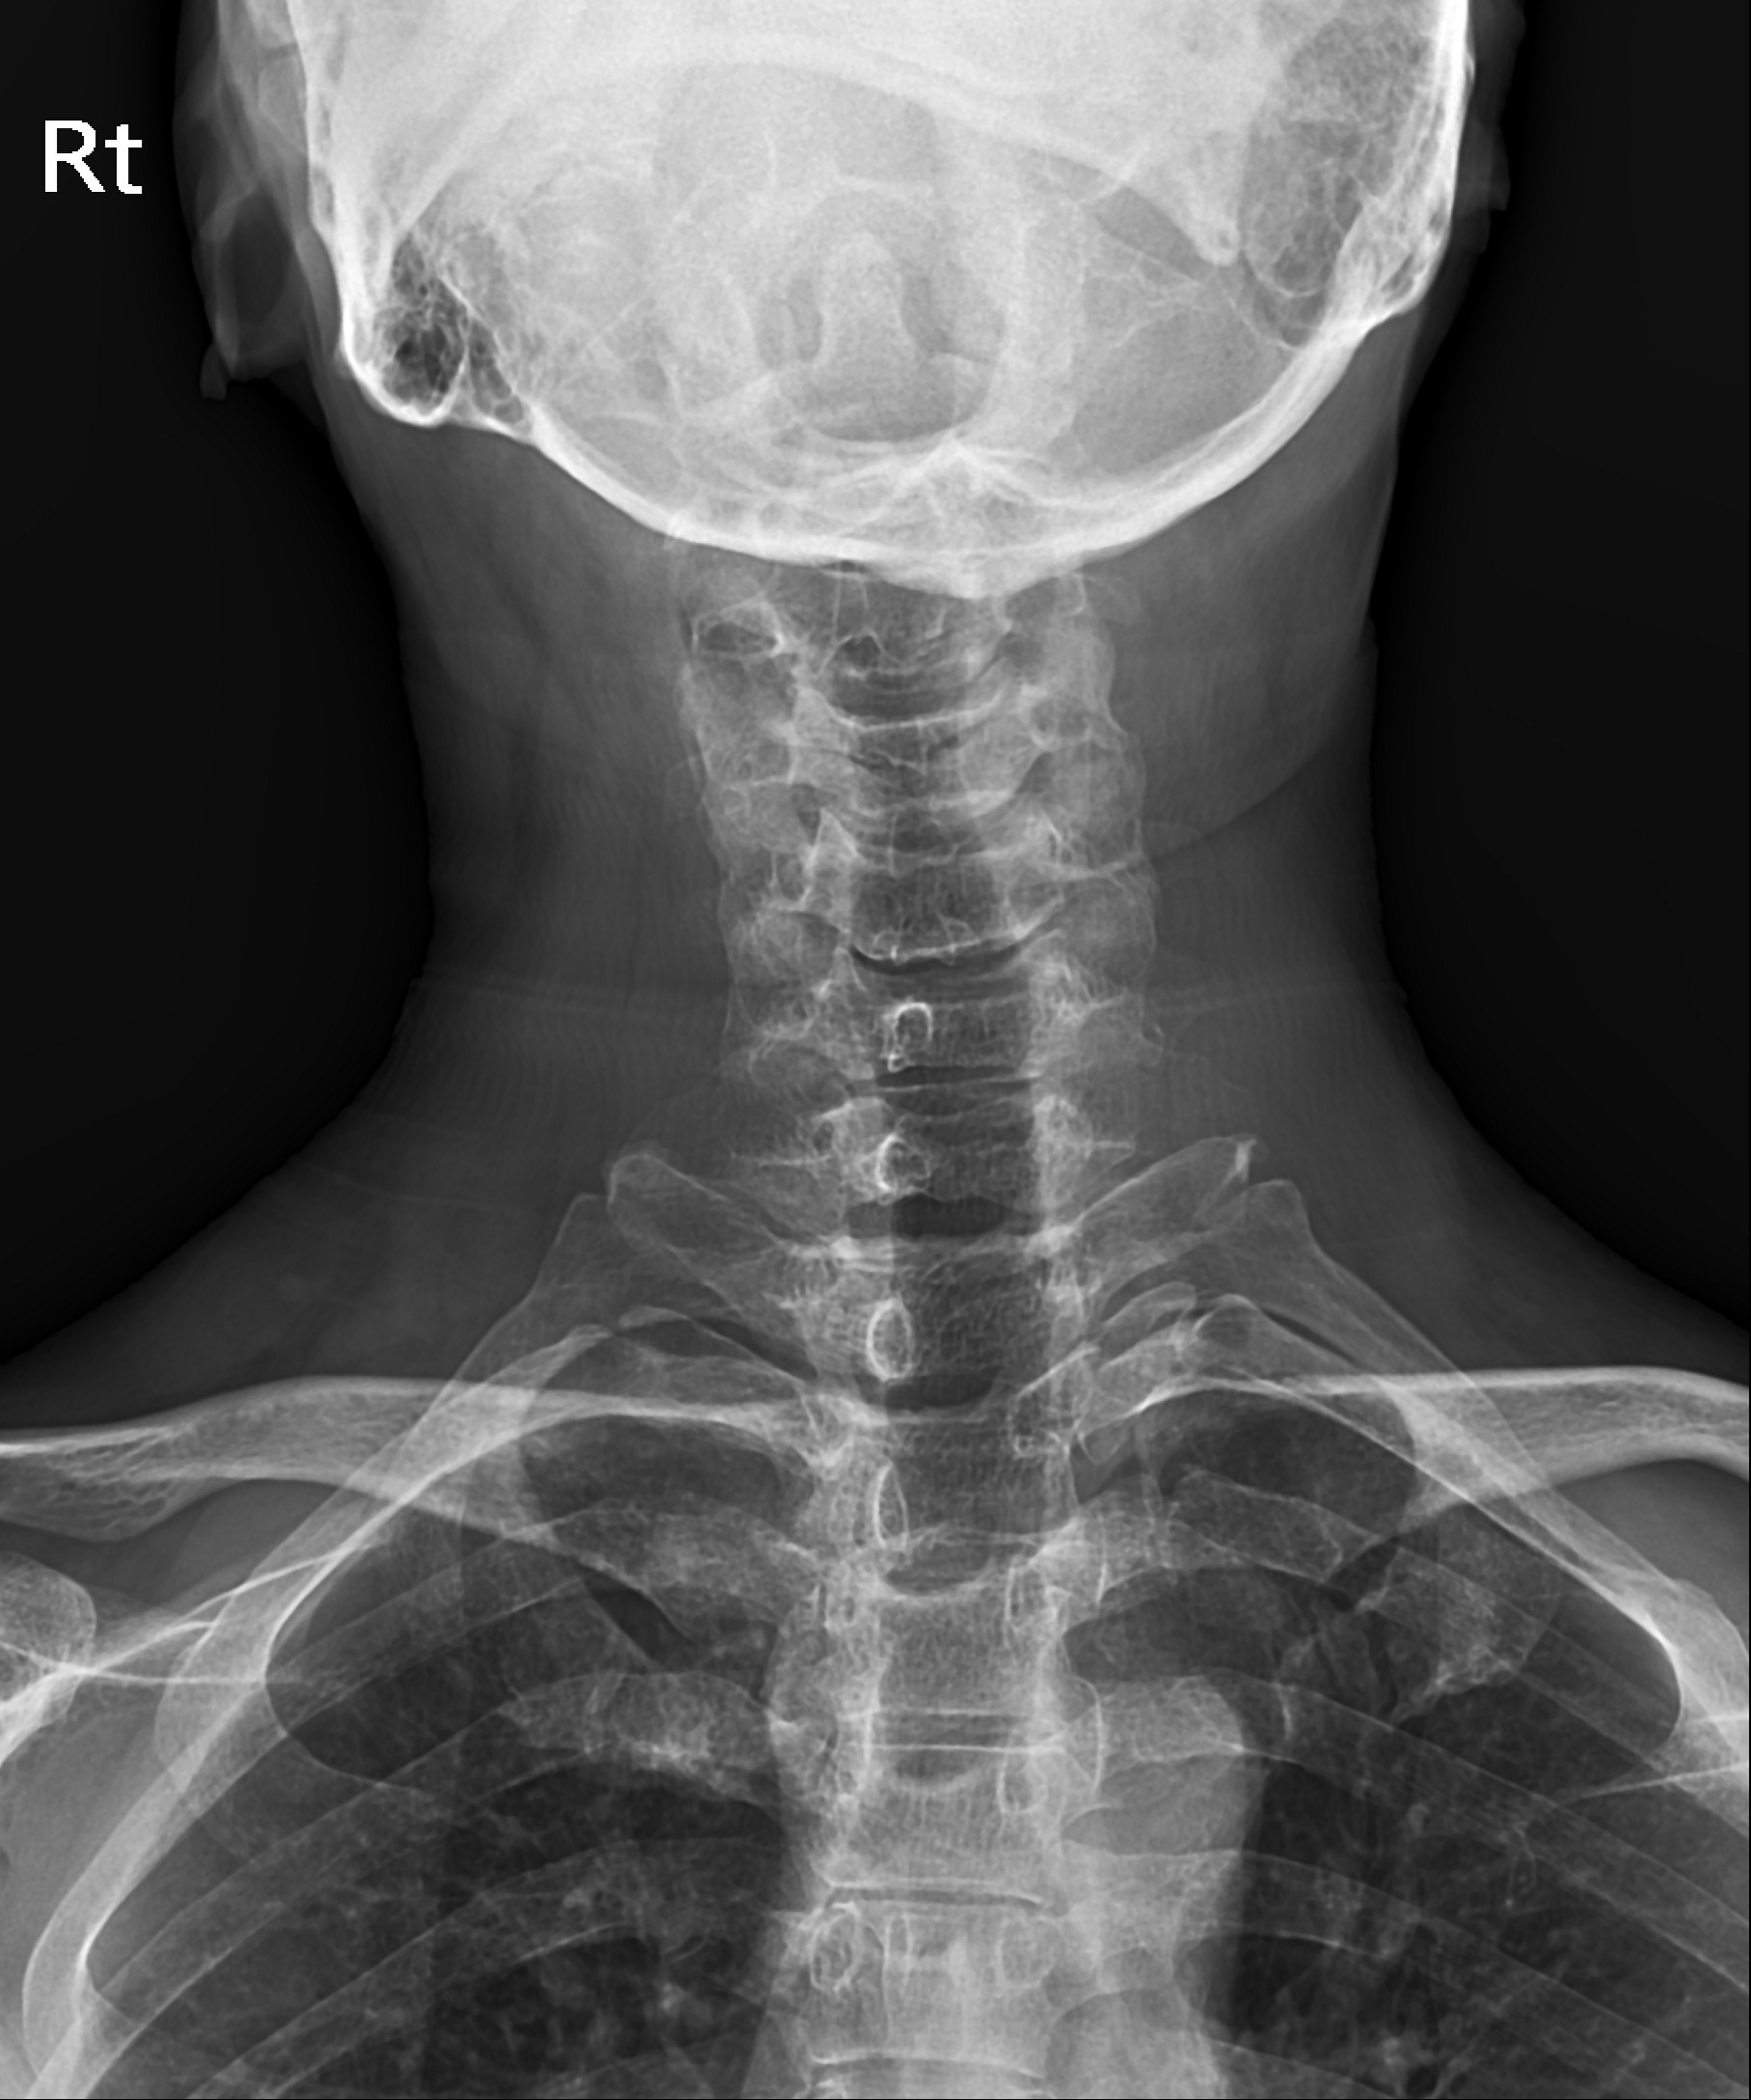

사경증 X-ray검사로 사경증 원인은 확인가능하다.

사경증 환자들의 목의 X-ray결과를 보면 경추부터 흉추, 요추까지 휘어있는 측만증과 같은 검사결과가 매우 많습니다. 일자목은 누구나 있고 등이 조금 휜 건 큰 병이 아니니까 그냥 살아도 되는 것이 아닙니다. 경추는 C커브가 반드시 되어야 하고 휘어진 척추는 바르게 교정해야 여러 가지 경추와 요추의 디스크, 협착증 등의 치료의 근본이 됩니다. 그러다 보면 사경증이라는 병명도 무색하게 자꾸자꾸 본래 모습대로 교정이 돼서 치료가 되는 것입니다. 그 후에 X-ray검사를 받아보면 경추가 바르고 두개골 균형, 척추의 라인도 정상으로 돌아가는 모습이 확인가능합니다.CBA장치를 이용한 턱관절 교정으로 경추를 바로 잡자.